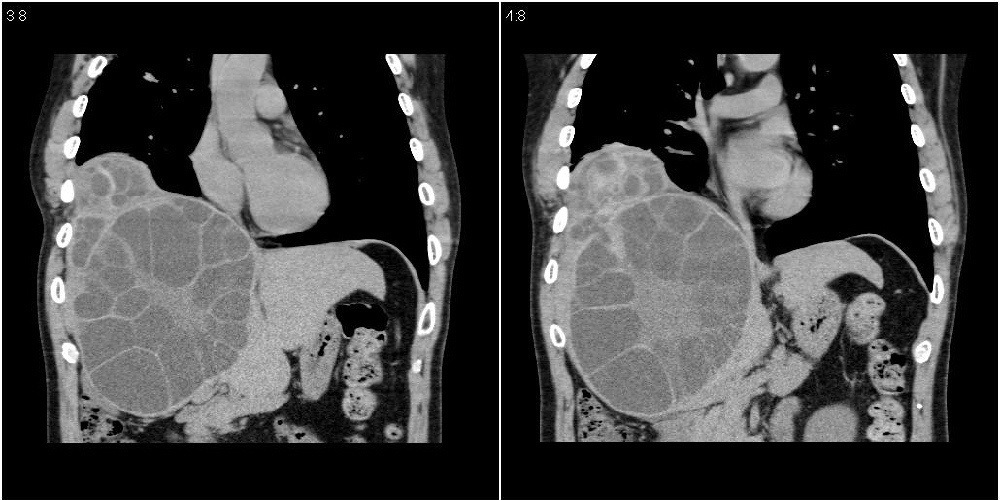

该患者70岁男性,手术后10年,现复查。2008年6月份本人曾经发过一极其类似的病例,只是部位略有差异。

多囊肝

肝脏多房性包虫囊肿

水上浮莲征,肝包虫囊肿。

肝脏及右侧胸腔包虫病。

大囊套小囊!肝脏多房性包虫囊肿